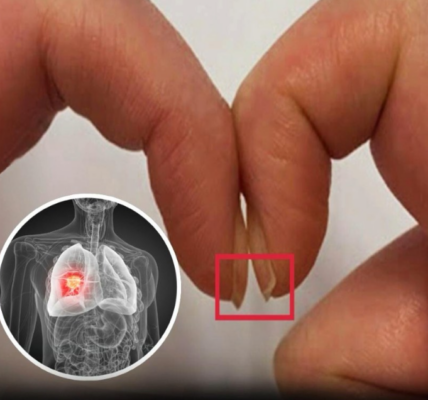

Wichtiges Warnzeichen für Krebs, das man nur nachts erkennen kann

Krebs ist eine verheerende Krankheit, und im Jahr 2025 werden in den Vereinigten Staaten unglaubliche 618.120 Menschen daran sterben. Wir alle kennen jemanden, der betroffen ist – deshalb sind Aufklärung und Früherkennung so wichtig. Erschreckenderweise überlebt nur die Hälfte aller…